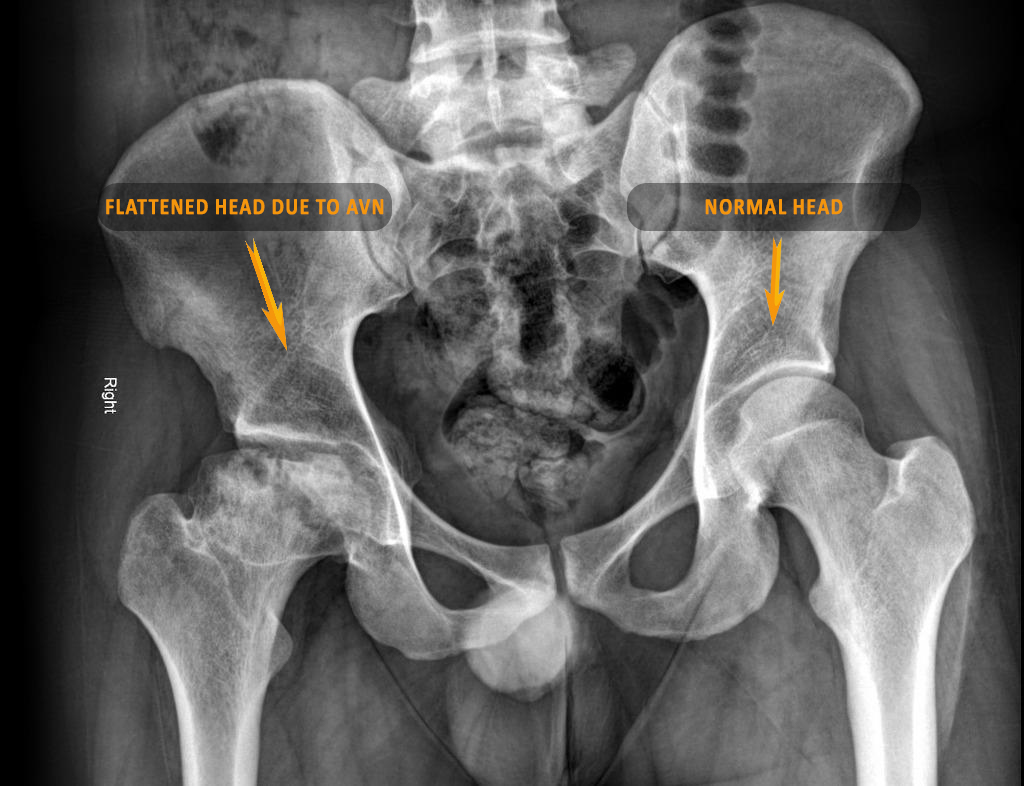

Avascular Necrosis (AVN) of the hip, although not life-threatening, is a rare but serious condition that is much more common in steroid-users. It is caused due to a decrease in the blood flow to the ball (head) of the thigh bone which makes up a part of the hip joint. As a result of the diminished blood flow, the bone in the ball starts to die out and becomes flattened.

Summary : Avascular Necrosis of the hip is a late complication seen increasingly in patients who have received steroid therapy for COVID-19. Any hip pain in such patients should be suspected as AVN and diagnosed and treated urgently. Early diagnosis and treatment can preserve the natural hip. Late presenting cases need to undergo a joint replacement surgery.